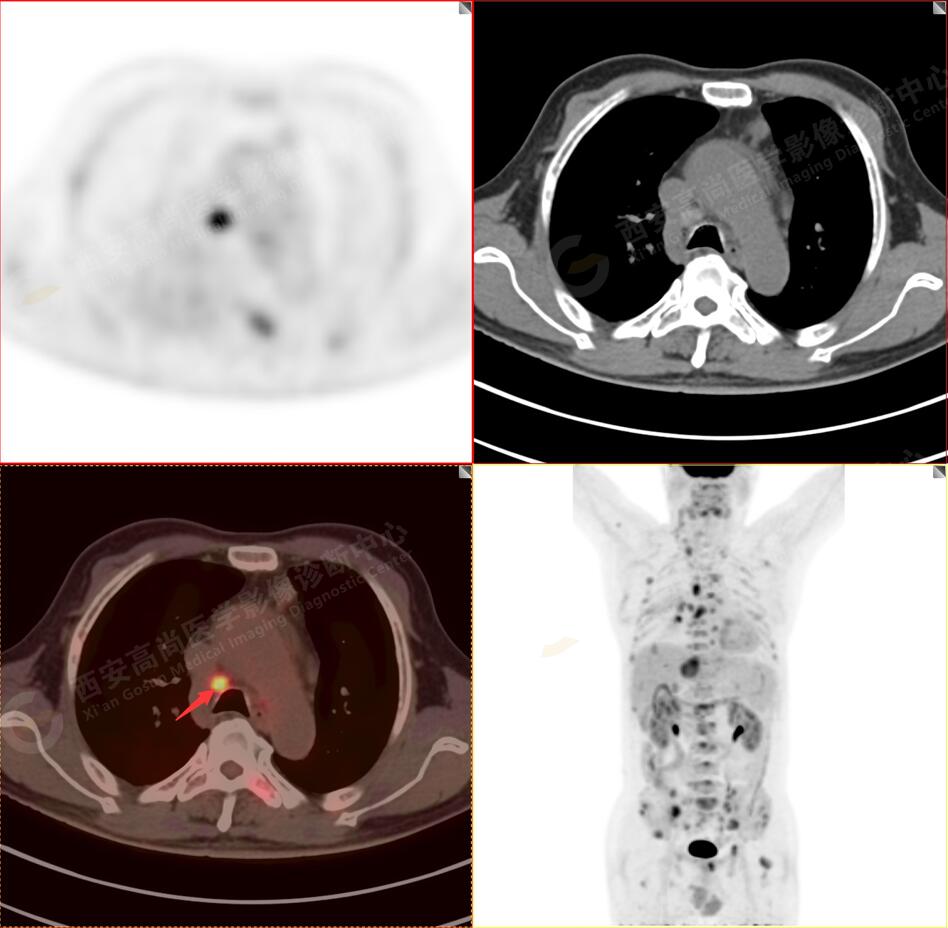

2.以下為全身多發(fā)轉移灶

3.右側頸部(Ⅱ-Ⅴ區(qū))、右側腋窩區(qū)、右側肺門及縱隔(1R、1L、2、4、6、7組)、肝門區(qū)多發(fā)腫大淋巴結,呈不同程度異常增高,均考慮為淋巴結轉移。

5.右側肱骨上段、左側肩胛骨、右側鎖骨胸骨端、胸骨、雙側多發(fā)肋骨、脊柱多發(fā)椎體及附件、雙側髂骨、雙側髖臼、雙側恥骨、雙側肱骨上段多發(fā)成骨性病變,呈不同程度FDG代謝異常增高,考慮為多發(fā)骨轉移瘤。